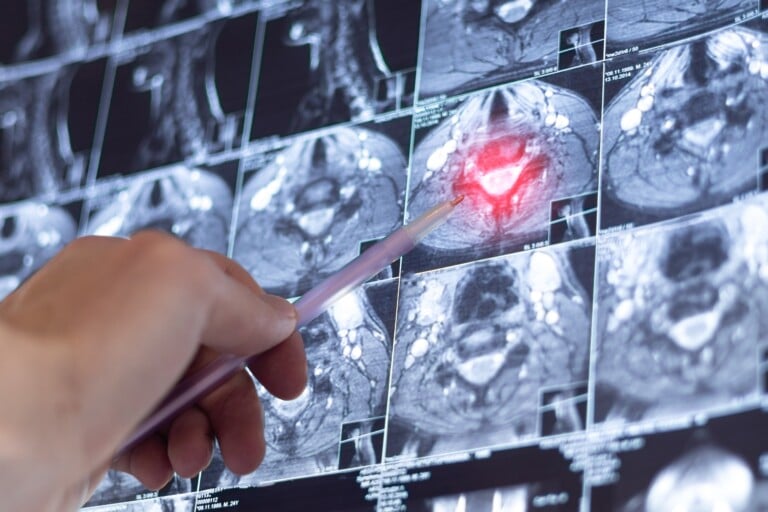

How MS is Diagnosed

Once MS is diagnosed using the McDonald criteria, which includes looking at medical history, doing a clinical exam, using magnetic resonance imaging (MRI), and conducting lab tests, the first treatment is usually intravenous steroids to manage the symptoms. Then, the physician creates an individualized treatment plan with disease-modifying therapies as the foundation of care.